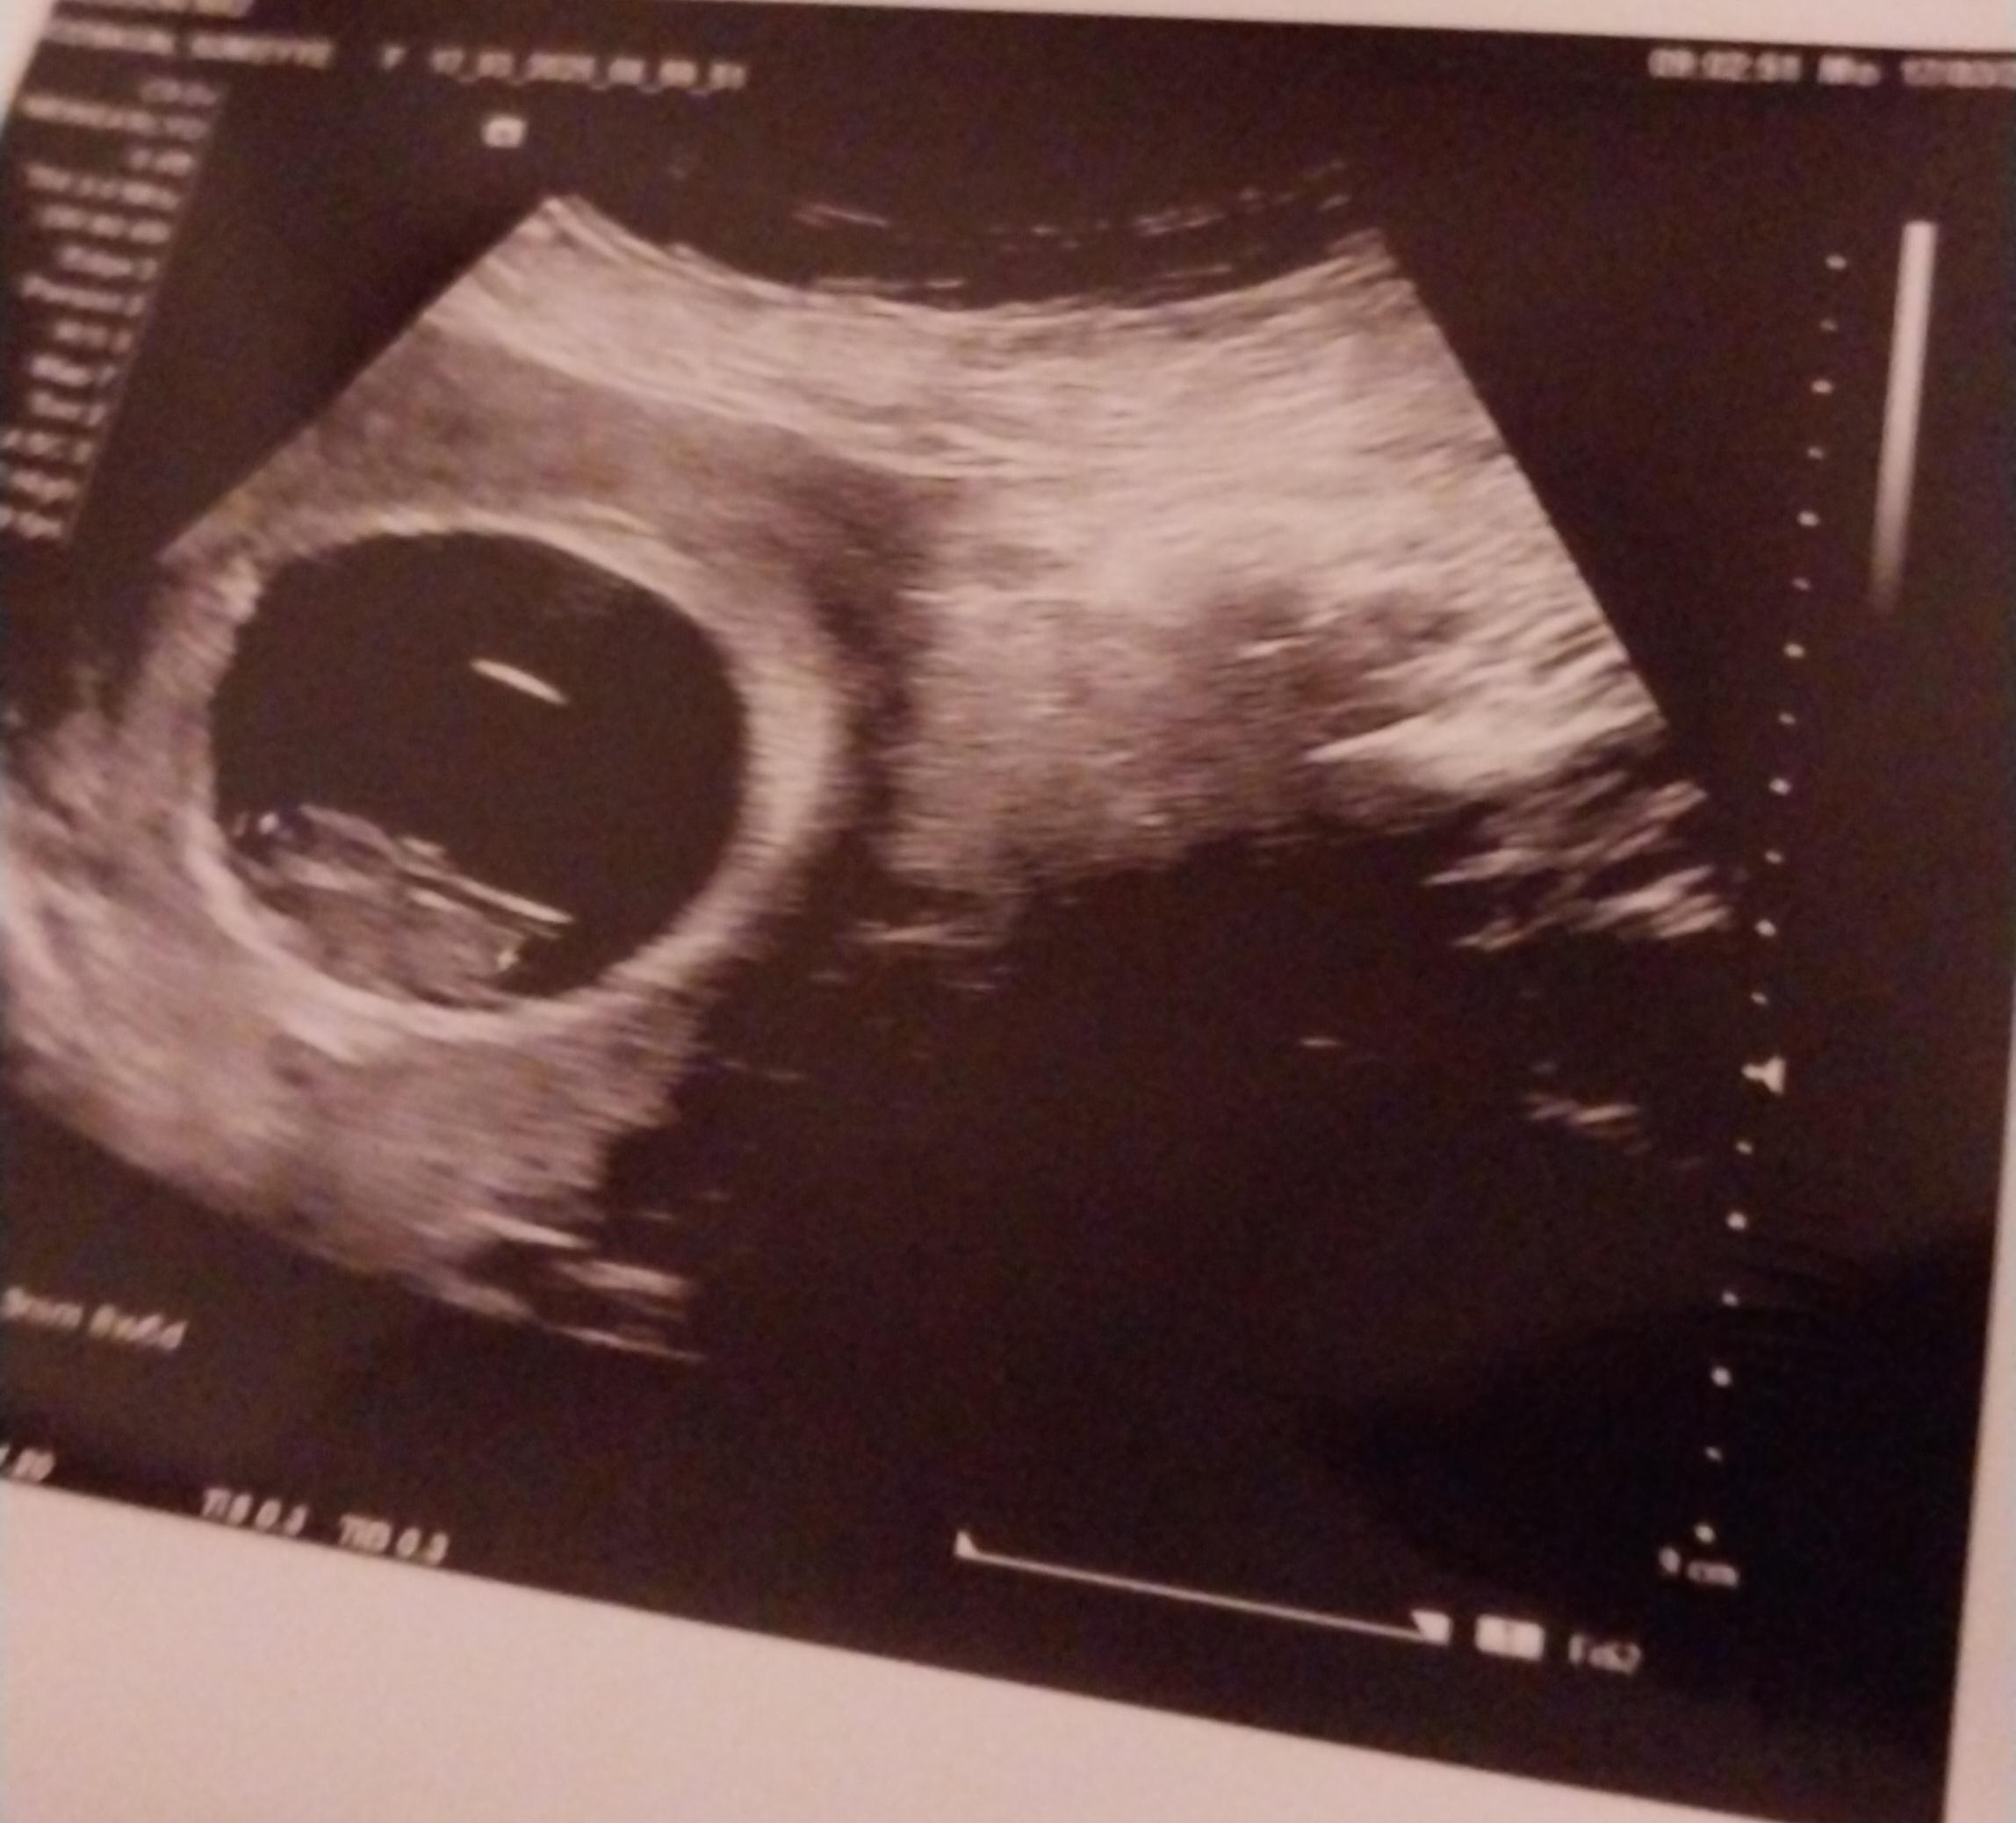

Cinsiyet tahmini

Konu Başlığı Cinsiyet tahmini